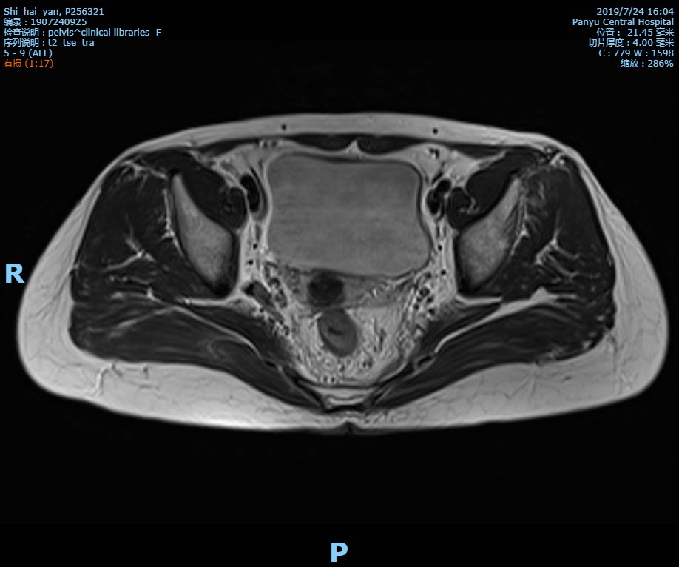

盆腔MR示:直肠全段管壁不均匀增厚,以中段较明显,最厚处约15mm,部分肠腔内见软组织肿块影突起,上下累及范围约70mm,距肛门距离约50mm,结肠浆膜面稍毛糙,局部与前筋膜分界不清,周围脂肪间隙部分略欠清;符合直肠癌改变,考虑累及浆膜面,不除外直肠前筋膜受累;

影像学检查资料: